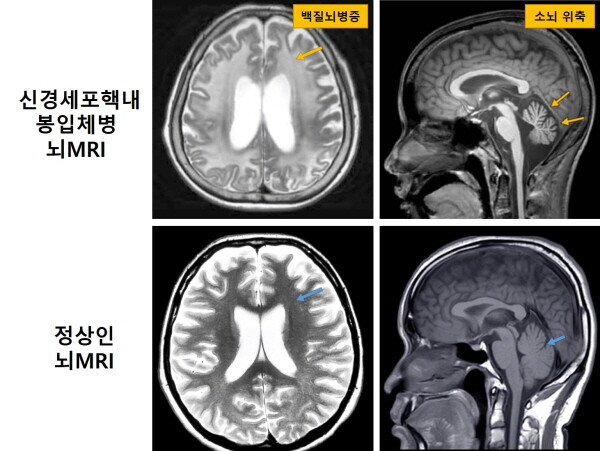

| ▲ 신경세포핵내봉입체병 환자 및 정상인의 뇌MRI 비교 (사진=서울대병원 제공) |

[mdtoday=이재혁 기자] 19세 환자 A씨는 9살부터 운동기능이 퇴행하면서 보행장애, 실조증과 같은 신경학적 증상을 앓았다. MRI에서 백질뇌병증과 소뇌 위축 소견이 나타났지만, 유전자 진단이 어려워 병명은 알 수 없었다. 그러다 A씨와 같은 증상을 앓던 누나가 16세 나이로 사망하면서 A씨와 그 가족에게는 정확한 진단명과 그에 따른 치료 계획 수립이 절실해졌다.

신경세포핵내봉입체병은 신경세포 핵 안에 비정상적인 단백질(봉입체)이 축적되는 신경퇴행성장애다. 발병 원인은 NOTCH2NLC 유전자에서 GGC 염기서열이 비정상적으로 반복되는 ‘단연쇄반복 변이’ 때문이다.

주로 성인기 발병하며 백질뇌병증, 진행성 인지기능 장애, 실조증과 같은 다양한 신경학적 증상을 동반한다.